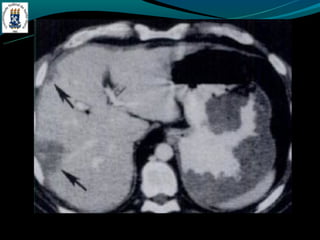

Peliose hepática